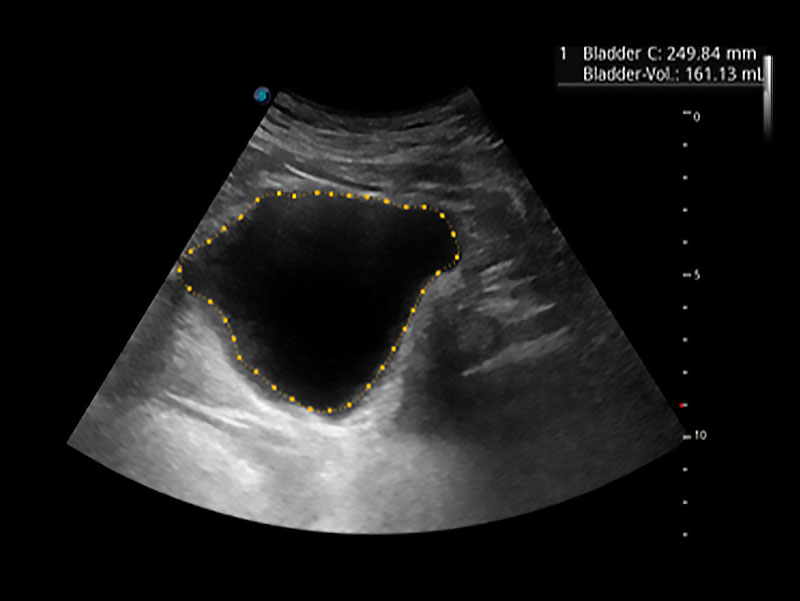

一鍵自動識別膀胱壁及自動測量膀胱容積,不受膀胱形狀和大小的限制,幫助醫(yī)生快速精準獲得測量的數(shù)據(jù)。